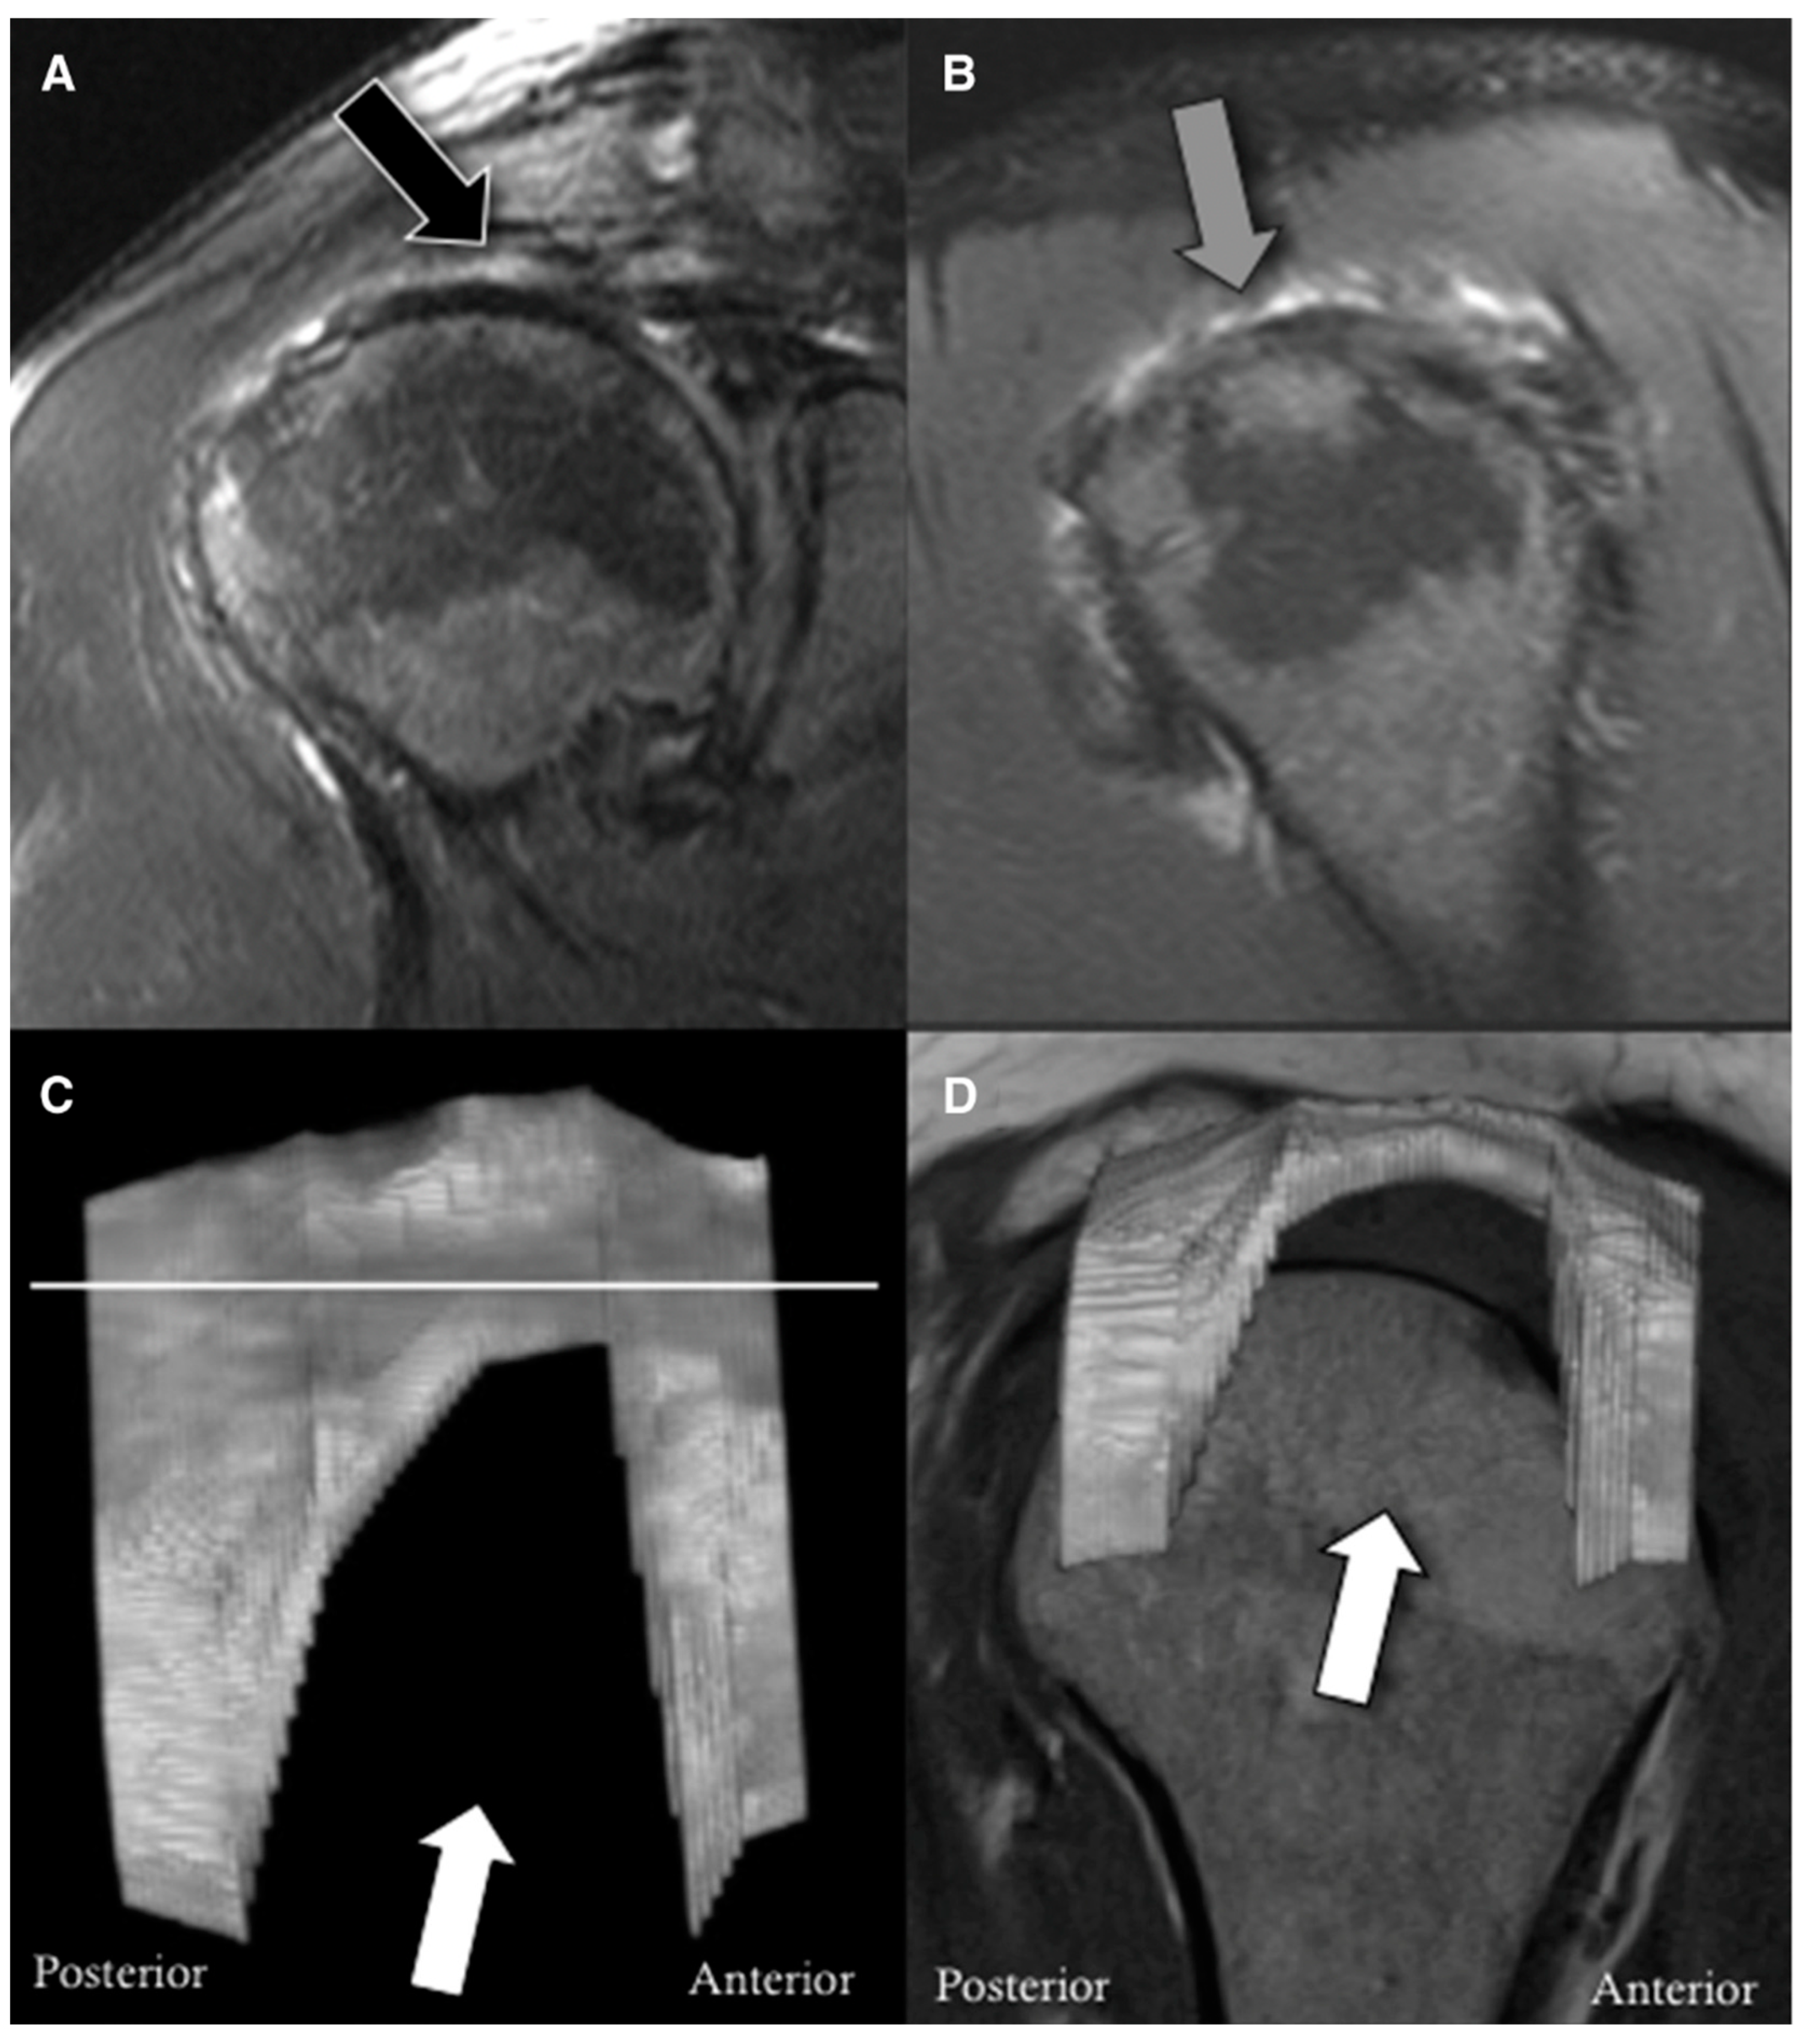

- Gyftopoulos, S.; Beltran, L.S.; Gibbs, K.; Jazrawi, L.; Berman, P.; Babb, J.; Meislin, R. Rotator cuff tear shape characterization: A comparison of two-dimensional imaging and three-dimensional magnetic resonance reconstructions. J. Shoulder Elb. Surg. 2015, 25, 22–30. [Google Scholar] [CrossRef]

- Werthel, J.-D.; de Casson, F.B.; Walch, G.; Gaudin, P.; Moroder, P.; Sanchez-Sotelo, J.; Chaoui, J.; Burdin, V. Three-dimensional muscle loss assessment: A novel computed tomography–based quantitative method to evaluate rotator cuff muscle fatty infiltration. J. Shoulder Elb. Surg. 2021, 31, 165–174. [Google Scholar] [CrossRef] [PubMed]

- Santago, A.C.; Vidt, M.E.; Tuohy, C.J.; Poehling, G.G.; Freehill, M.T.; Jordan, J.H.; Kraft, R.A.; Saul, K.R. Quantitative Analysis of Three-Dimensional Distribution and Clustering of Intramuscular Fat in Muscles of the Rotator Cuff. Ann. Biomed. Eng. 2015, 44, 2158–2167. [Google Scholar] [CrossRef] [PubMed]

- Nozaki, T.; Tasaki, A.; Horiuchi, S.; Osakabe, C.; Ohde, S.; Saida, Y.; Yoshioka, H. Quantification of Fatty Degeneration Within the Supraspinatus Muscle by Using a 2-Point Dixon Method on 3-T MRI. Am. J. Roentgenol. 2015, 205, 116–122. [Google Scholar] [CrossRef]